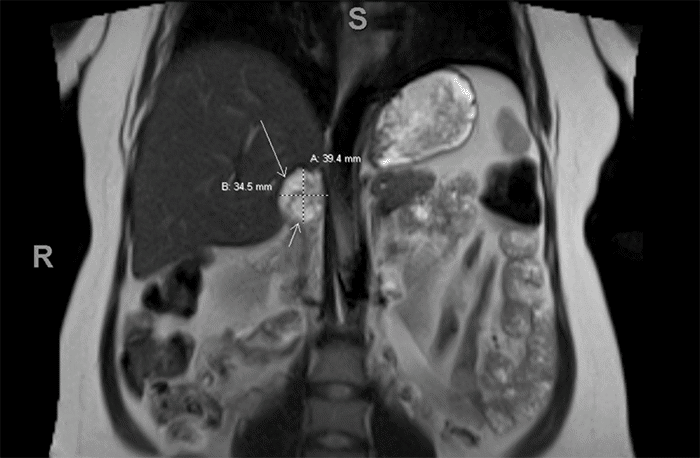

Biochemical testing at 31 weeks gestation revealed significantly elevated urine normetanephrine (4630 mcg/24 hour; normal 35-482 mcg/24 hour) and total metanephrine (4786 mcg/24 hour; normal 115-695 mcg/24 hour) levels, while catecholamine levels were within normal range. Subsequent magnetic resonance imaging (MRI) of the chest, abdomen, and pelvis revealed a 3.4 × 3.6 × 3.9 cm heterogenous mass in the right adrenal gland (Figures 1-3), consistent with pheochromocytoma.

Figure 3. Sagittal View of T2-Weighted MRI Showing Patient at 31 weeks Gestation. Published With Permission